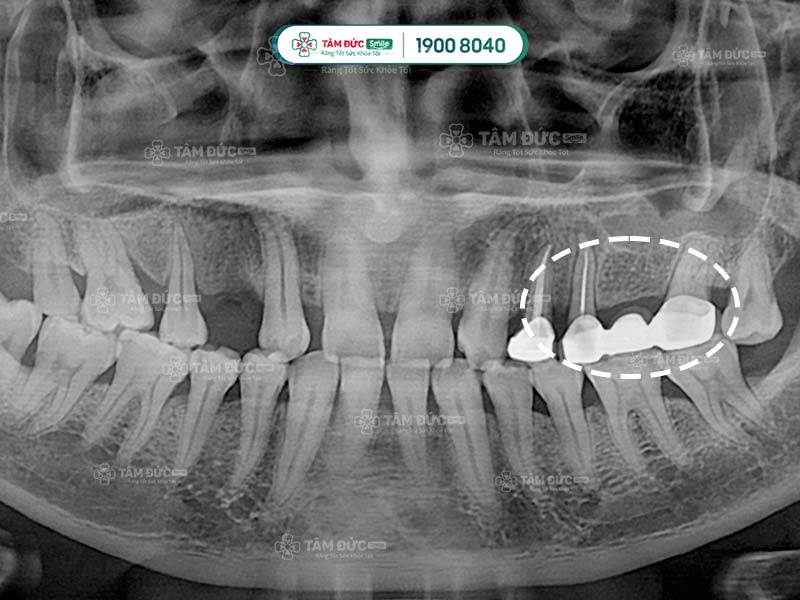

hình cầu răng sứ qua phim chụp x-quang

Cầu răng sứ qua phim X-Quang